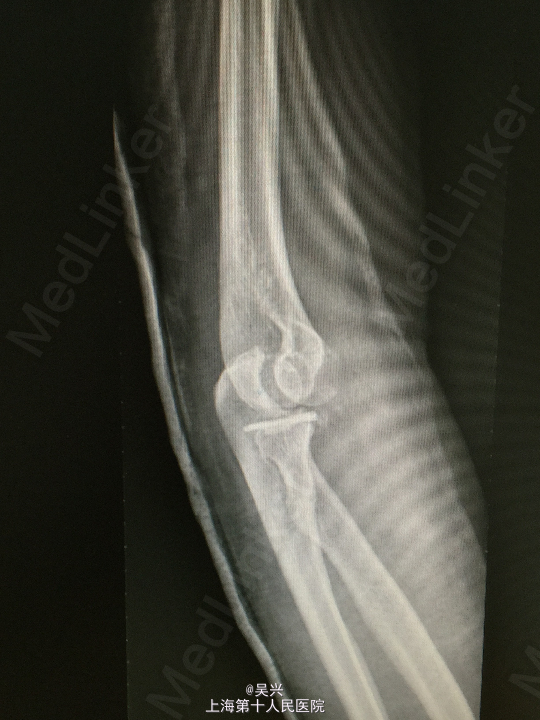

左肘外伤肿痛畸形3小时。左肘屈曲位着地受伤。

急症查体见肘关节肿胀、触痛,存在向后方半脱位及外侧松弛不稳定。

诊断:左肘恐怖三联症。 处理:术前准备,抗炎消肿治疗,术后三天行左肘正中切口显露尺骨冠状突,术中见尺骨冠状突粉碎性骨折,用两枚微型空心螺钉固定,发现屈肘位置仍有肘关节半脱位趋向。予伸肘位石膏固定,术后2周改屈肘45度位石膏固定,术后4周拆石膏,能逐渐屈肘至90度。

随访:术后1月患者肘关节稳定性良好,伸肘0度,屈肘90度,理疗辅助功能锻炼中。 讨论:肘关节脱位(半脱位)伴尺骨冠状突骨折、桡骨小头骨折称为肘关节恐怖三联症。该症存在极度肘关节不稳定,容易发生向后方、侧方脱位。一般单纯尺骨冠状突骨折极少,多伴有桡侧结构损伤和关节不稳定。肘关节恐怖三联症治疗原则一般是复位固定尺骨冠状突和桡骨小头,修复桡侧副韧带。我们术中发现固定尺骨冠状突后关节仍然不稳定,但桡骨小头因不全骨折需要石膏固定,因此不采取手术修复外侧副韧带,而是石膏固定,术后也取得较好的效果。